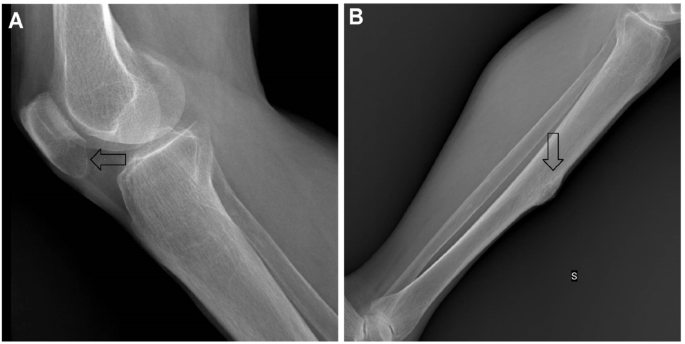

Il tumore bruno è una lesione dell'osso che può insorgere quando l'attività degli osteoclasti aumenta eccessivamente, come ad esempio in corso di iperparatiroidismo A dispetto del nome, non si tratta di un vero tumore, anche se può essere scambiato per tale I tumori bruni hanno aspetto radiotrasparente ai raggi x. Bruno had an oncology checkup and unfortunately they found a lump on his left temple It was aspirated and confirmed to be a mast cell tumor When a tumor is aspirated it means they put a needle into the lump and pull out cells to be tested The fluid that was extracted has been sent away for more testing. This page was last edited on 25 February 19, at 1549 Files are available under licenses specified on their description page All structured data from the file and property namespaces is available under the Creative Commons CC0 License;.

Tumore bruno Il tumore bruno è una lesione dell'osso che può insorgere quando l'attività degli osteoclasti aumenta eccessivamente, come ad esempio in corso di iperparatiroidismo 2 relazioni Iperparatiroidismo , Osteodistrofia renale. Tumore bruno Il tumore bruno è una lesione dell'osso che può insorgere quando l'attività degli osteoclasti aumenta eccessivamente, come ad esempio in corso di iperparatiroidismo 2 relazioni Iperparatiroidismo , Osteodistrofia renale. Gammadelta T cells are a subgroup of white blood cells that have the ability to effectively eliminate tumor cells Bruno Silva Santos's research group has been studying the biology of these cells.

Tumore bruno Il tumore bruno è una lesione dell'osso che può insorgere quando l'attività degli osteoclasti aumenta eccessivamente, come ad esempio in corso di iperparatiroidismo 2 relazioni Iperparatiroidismo, Osteodistrofia renale. Hepatic adrenal rest tumors (HART), previously been termed primary hypernephroma of the liver or hypernephroid carcinoma of the liver, are very rare liver tumors with histology similar to adrenocortical carcinoma Epidemiology It tends to occu. Breast cancer cells were Foxp3 in 57% of tumors Foxp3 expression in breast cancer cells was associated with better relapsefree (P = 0005) and overall survival (P = 003) By multivariate analysis, the presence of Foxp3 tumor cells produced an independent prognostic factor for both better relapsefree (P = 0006) and overall survival (P = 0.

©12, Genentech©17, Genentech Drugdisease modeling framework Bruno et al Clin Pharmacol Ther, , 13 2 Modelsbased tumor growth inhibition (TGI) metrics (tumor growth rate) as. Tumore bruno Il tumore bruno è una lesione dell'osso che può insorgere quando l'attività degli osteoclasti aumenta eccessivamente, come ad esempio in corso di iperparatiroidismo 2 relazioni Iperparatiroidismo , Osteodistrofia renale. Il tumore è molto vascolarizzato e si presenta come massa soffice con un colore bruno che deriva dalla pigmentazione emosiderinica, in conseguenza ai frequenti processi emorragici che avvengono nella massa tumorale La sintomatologia della neoplasia consiste in dolore e tumefazione locale secondo la sede della neoplasia;.

During the 62nd American Society of Hematology (ASH) Annual Meeting and Exposition, the Multiple Myeloma Hub spoke to Bruno Paiva, University of Navarra, Pamplona, ES We asked, Can circulating tumor cell assessment by flow replace bone marrow aspirates to monitor smoldering multiple myeloma (SMM)?. Il tumore bruno è una lesione dell'osso che può insorgere quando l'attività degli osteoclasti aumenta eccessivamente, come ad esempio in corso di iperparatiroidismo A dispetto del nome, non si tratta di un vero tumore, anche se può essere scambiato per tale I tumori bruni hanno aspetto radiotrasparente ai raggi x. Additional terms may apply.